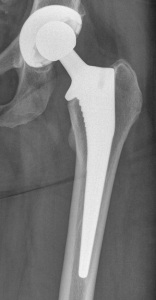

PROFILE TRAINING AND PRESENTATION Dr. Niranjanan Recieving Diploma SICOT degree in Rome, Italy Dr. Niranjanan being awarded fellowship certificate at Indian spinal injuries centre CLIINIC SOME OF Dr. NIRANJANAN's CASES